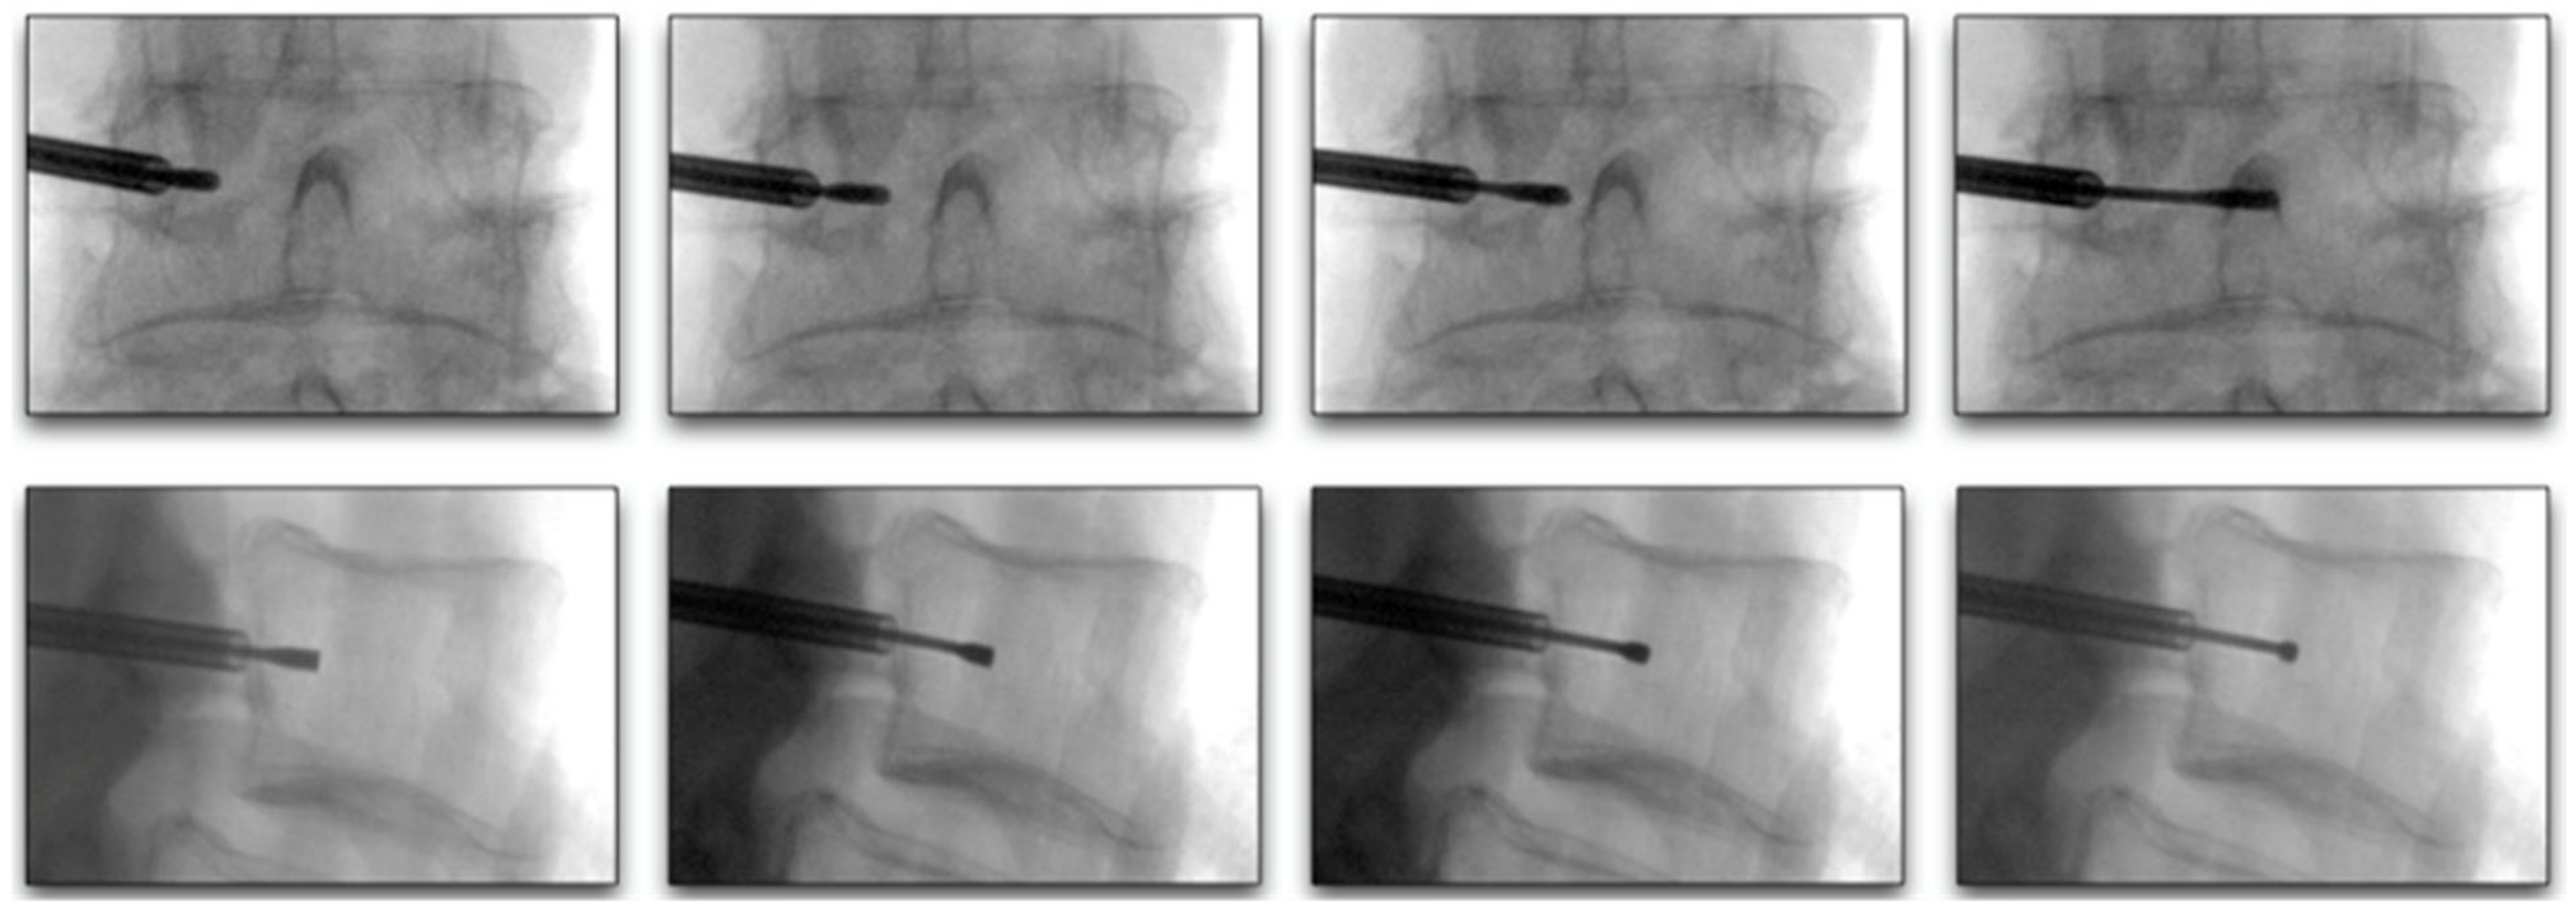

- Nguyen, K.M.L.; Nguyen, D.T.D. Minimally invasive treatment for degenerative lumbar spine. Tech. Vasc. Interv. Radiol. 2020, 23, 100700. [Google Scholar] [CrossRef]

- Michalik, A.; Conger, A.; Smuck, M.; Maus, T.P.; McCormick, Z.L. Intraosseous basivertebral nerve radiofrequency ablation for the treatment of vertebral body endplate low back pain: Current evidence and future directions. Pain Med. 2021, 22, S24–S30. [Google Scholar] [CrossRef] [PubMed]

- Tieppo Francio, V.; Sherwood, D.; Twohey, E.; Barndt, B.; Pagan-Rosado, R.; Eubanks, J.; Sayed, D. Developments in minimally invasive surgical options for vertebral pain: Basivertebral nerve ablation—A narrative review. J. Pain Res. 2021, 14, 1887. [Google Scholar] [CrossRef] [PubMed]